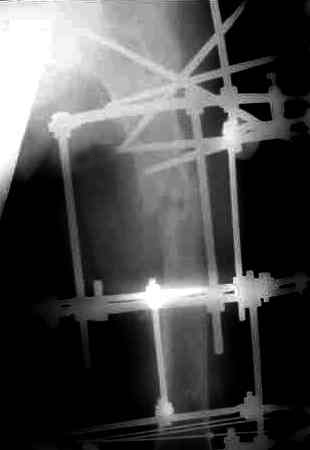

Через 3 года после травмы констатировало отсутствие консолидации бедренной кости, сохранение признаков хронического остеомиелита (свищ в нижней трети левого бедра). Произведен демонтаж аппарата, реостеосинтез бедренной кости спице-стержневым аппаратом, некрсеквестрэктомия. В аппарате удалось лишь частично произвестиустранение углообразной деформации бедренной кости [image 05] .